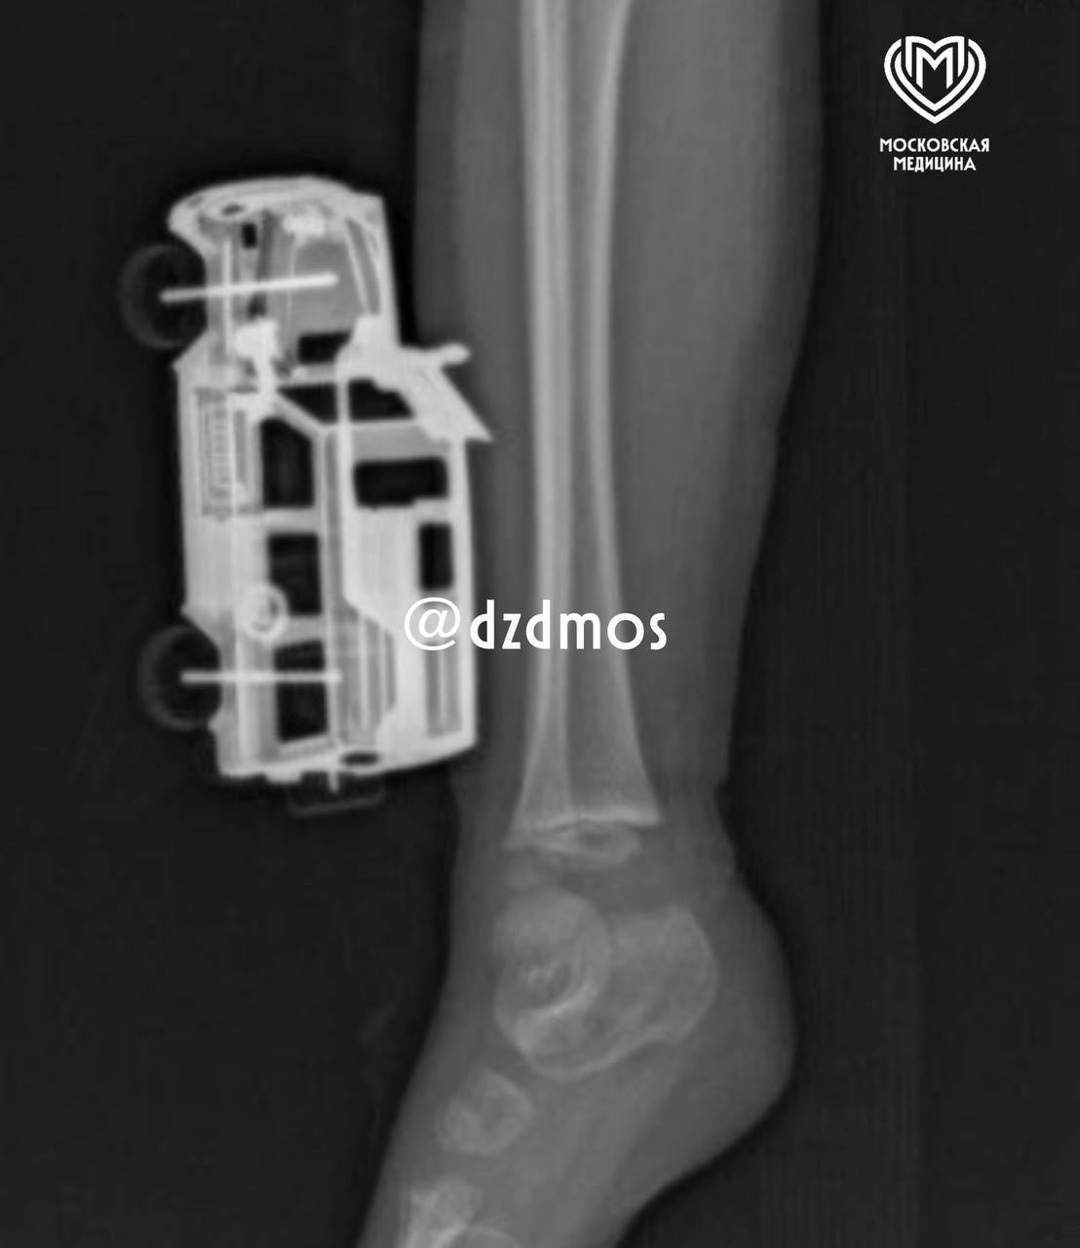

ИСТОРИЯ СПАСЕНИЯ: ВРАЧИ ДЕТСКОЙ БОЛЬНИЦЫ ИМ. Г.Н. СПЕРАНСКОГО СПАСЛИ МАЛЬЧИКА С ИГРУШЕЧНОЙ МАШИНКОЙ В ГОЛЕНИ

Столичные детские врачи спасли 4-х летнего мальчика с металлической игрушечной машинкой в голени

Детская шалость привела к травме. Со слов родителей, ребёнок прыгнул с кровати и неудачно приземлился на игрушку. Машинка не только повредила мягкие ткани правой голени, а её части вошли в них достаточно глубоко — до подкожножировой клетчатки. Родители вызвали  скорую помощь и мальчика привезли в больницу Сперанского.

«Маленькому пациенту сделали рентгенографию, чтобы исключить повреждения костей голени и понять глубину повреждения. Затем удалили игрушку и выполнили хирургическую обработку серьёзной раны. Через сутки энергичного детсадовца выписали домой под амбулаторное наблюдение», — рассказал Магомед Шихахмедов, травматолог-ортопед отделения экстренной хирургической помощи.